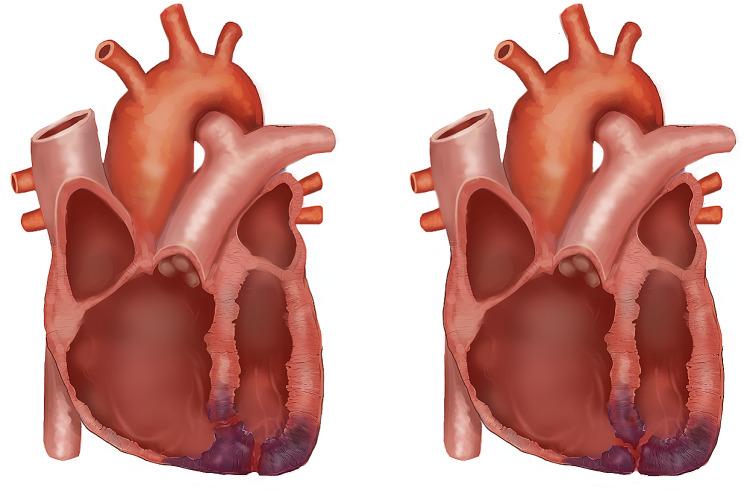

Left ventricular free wall rupture (LVFWR) and interventricular septal rupture (VSR) are potentially catastrophic mechanical complications after acute myocardial infarction (AMI). When they occur together, "double myocardial rupture" (DMR), survival is unlikely. DMR is seen in only 0.3% of all AMIs. With or without surgical intervention, the odds are against the patient.

左心室游离壁破裂(LVFWR)和室间隔破裂(VSR)是急性心肌梗死(AMI)后潜在的灾难性机械并发症。当它们同时发生时,称为“双心肌破裂”(DMR),患者几乎不可能存活。DMR 仅见于所有 AMI 的 0.3%。无论是否进行手术干预,患者的存活几率都很小。